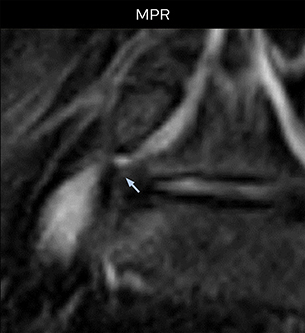

“Recently, the two surgical methods extreme and oblique lateral interbody fusion (XLIF and OLIF) have become mainstream for minimally invasive treatment of lumbar spinal canal stenosis and intervertebral foramen stenosis. With these surgical techniques, the spine is approached from the flank, and prior knowledge of the exact anatomy of the lumbosacral plexus would be extremely helpful. To that end, high slice resolution (less than 1 mm acquisition) that enables sharper sagittal MPR images will be needed.”

“For both brachial and lumbar plexus, we are currently using a 230 mm FOV and voxels of about 1 x 1 x 2 mm acquired (1 x 1 x 1 mm reconstructed). This provides us a good representation of the nerves, even though this FOV is relatively small. Regarding the inplane resolution, we hope to be able to bring that down to 0.7 mm, similar to our typical 2D multislice T2W images,” says Tanji.

“The intra-luminal signal of veins, especially around the intervertebral space, can be suppressed well with NerveVIEW. As a result, we can easily observe the detailed nerve structure around the posterior ganglion,” he says. “This is why we use 3D NerveVIEW for intraforaminal stenosis and extraforaminal stenosis/herniation (lateral disc herniation). On the other hand, if herniation is suspected to exist inside the dorsal root ganglion (DRG), balanced TFE or ProSet-FFE is applied. NerveVIEW is not suitable for evaluating the median type of herniation.” The SE-EPI DWI-based method for MR neurography works well for large FOV exams like whole-body MRI, but focal examination of nerves is often limited by the attainable spatial resolution (both inplane and slice direction) and geometric distortion. “3D NerveVIEW achieves higher in-plane resolution – close to our other routine spine sequences – and the source images can be used instead of adding a fat-suppressed T2-weighted sequence,” Tanji says.